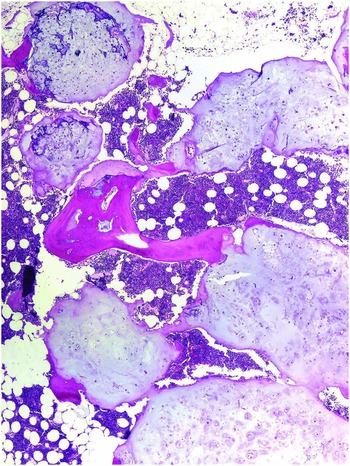

61g3pHBqBoL._AC_UF1000,, Diagnosis of bone and joint disorders : Resnick, Donald,

Diagnosis of bone and joint disorders : Resnick, Donald, Diagnosis of Bone and Joint Disorders: Resnick, Donald,

Diagnosis of Bone and Joint Disorders: Resnick, Donald, Diagnosis of Bone and Joint Disorders: Resnick, Donald,

Diagnosis of Bone and Joint Disorders: Resnick, Donald, 61sa2nN44qL.jpg,

61sa2nN44qL.jpg, fendo-13-819641-g001.jpg,

fendo-13-819641-g001.jpg, Diagnosing bone disease (Chapter 1) - Pathology of Bone and,

Diagnosing bone disease (Chapter 1) - Pathology of Bone and, Diagnosis of Joint Disorders | SpringerLink,